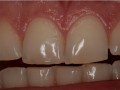

Bezpośrednia licówka kompozytowa w odcinku przednim wykonana…